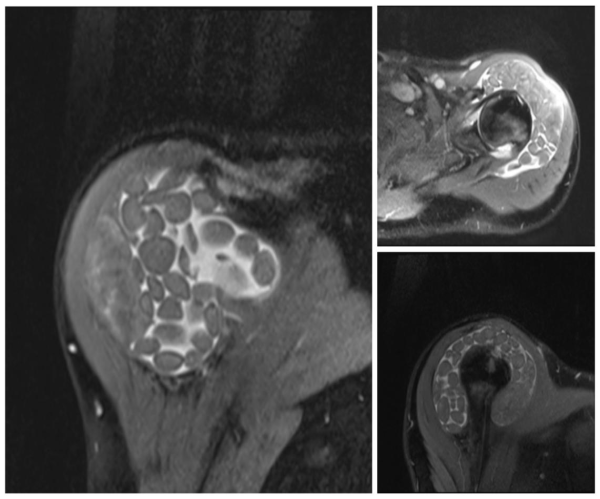

患者为57岁男性,有长期类风湿关节炎病史,左肩部包块伴疼痛、活动受限已五年余,经保守治疗效果不佳。骨科主任周歧勇组织团队评估后,由黄彭林主治医师主刀,为患者实施了开放性滑囊炎切除术。术中,在患者肩峰下滑囊内发现了大量白色、直径3-8毫米的“米粒体”,共计摘除近200枚。手术历时一小时,过程顺利。

图2:术中所见